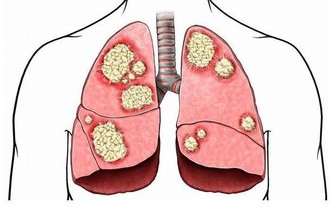

以上12點現像沒有一兩項以上就要養肝護肝了。肝出問題,容易誘發疾病。

中醫認為「養肝就是養命」。如果肝臟代謝不正常,人體所需的養分得不到及時供應,身體各個器官都無法正常工作:本應明亮的眼睛會由於肝血不足而 乾澀 呆滯,本應光滑堅韌的指甲也會幹枯變形。如果肝臟無法正常排毒,毒素就會滯留在體內,再美的女人也會變成「黃臉婆」,再強壯的男人也會萎靡不振。要想身體 好,首先要保護好肝臟,這就是中醫所說的「養肝就是養命」。